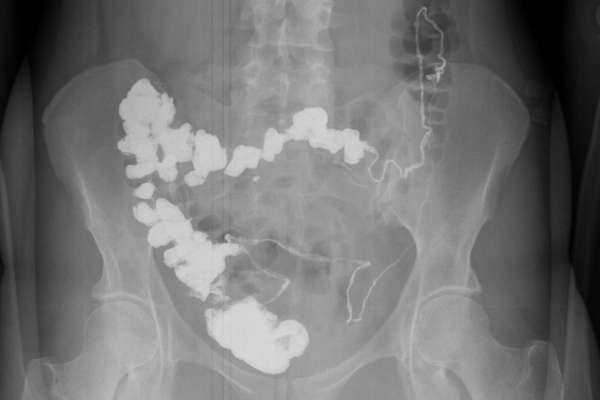

Введение рентгеноконтрастного вещества в верхние отделы ЖКТ (через рот или назогастральный зонд (НГЗ)) с получением серии рентгенограмм для исследования продвижения контраста по тонкой кишке в толстую.

а) Преимущества пробы Шварца:

• Оценка анатомических особенностей, конфигурации, диаметра, длины (например, после предшествующих резекций), стриктур, свищей, изменений слизистой и т.д.

• Оценка функции: время пассажа, замедленное продвижение контраста.

• Выявление уровня обструкции.

б) Ограничения пробы Шварца. Ограниченные возможности для оценки состояния слизистой по причине наложения петель друг на друга.

Исследование пассажа бария по тонкой кишке

а) Цель. Исследование тонкой кишки с наилучшим контрастированием (плановое).

б) Оборудование и методика. Обзорный снимок. Назначение одного стакана жидкого бария внутрь => серия снимков в соответствующие интервалы времени. Если контраст не достиг толстой кишки в течение 4 часов => поздние снимки (например, через 24 часа).